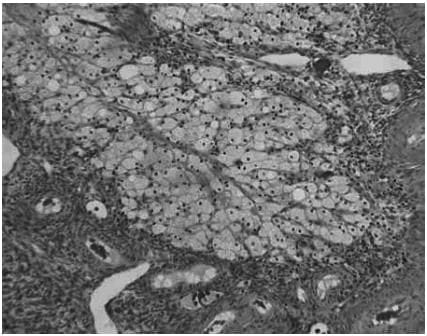

The histological appearances of the corpus luteum, showing

(a) an active corpus luteum

(b) regression of the corpus luteum with histiocyte infiltration